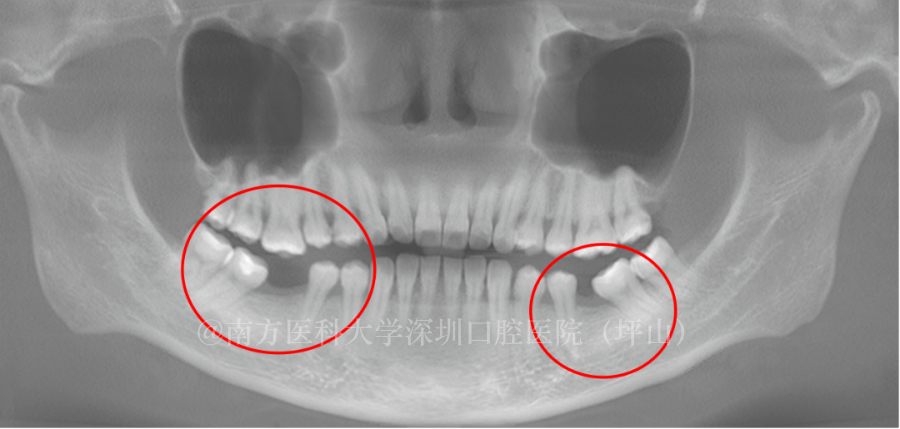

▲乳牙龋坏导致恒牙异位萌出

比如,这个娃的门牙和六龄牙是刚换的,是好的,但是其他乳牙都坏了,甚至有根尖炎,恒牙不能从原本的位置萌出,只能从其他位置出来,导致恒牙的异位萌出。

所以,乳牙龋坏一定要治疗,它不仅会影响恒牙的萌出,还可能导致这个娃前面牙弓长度缩短,将来大概率会出现牙列拥挤的问题。